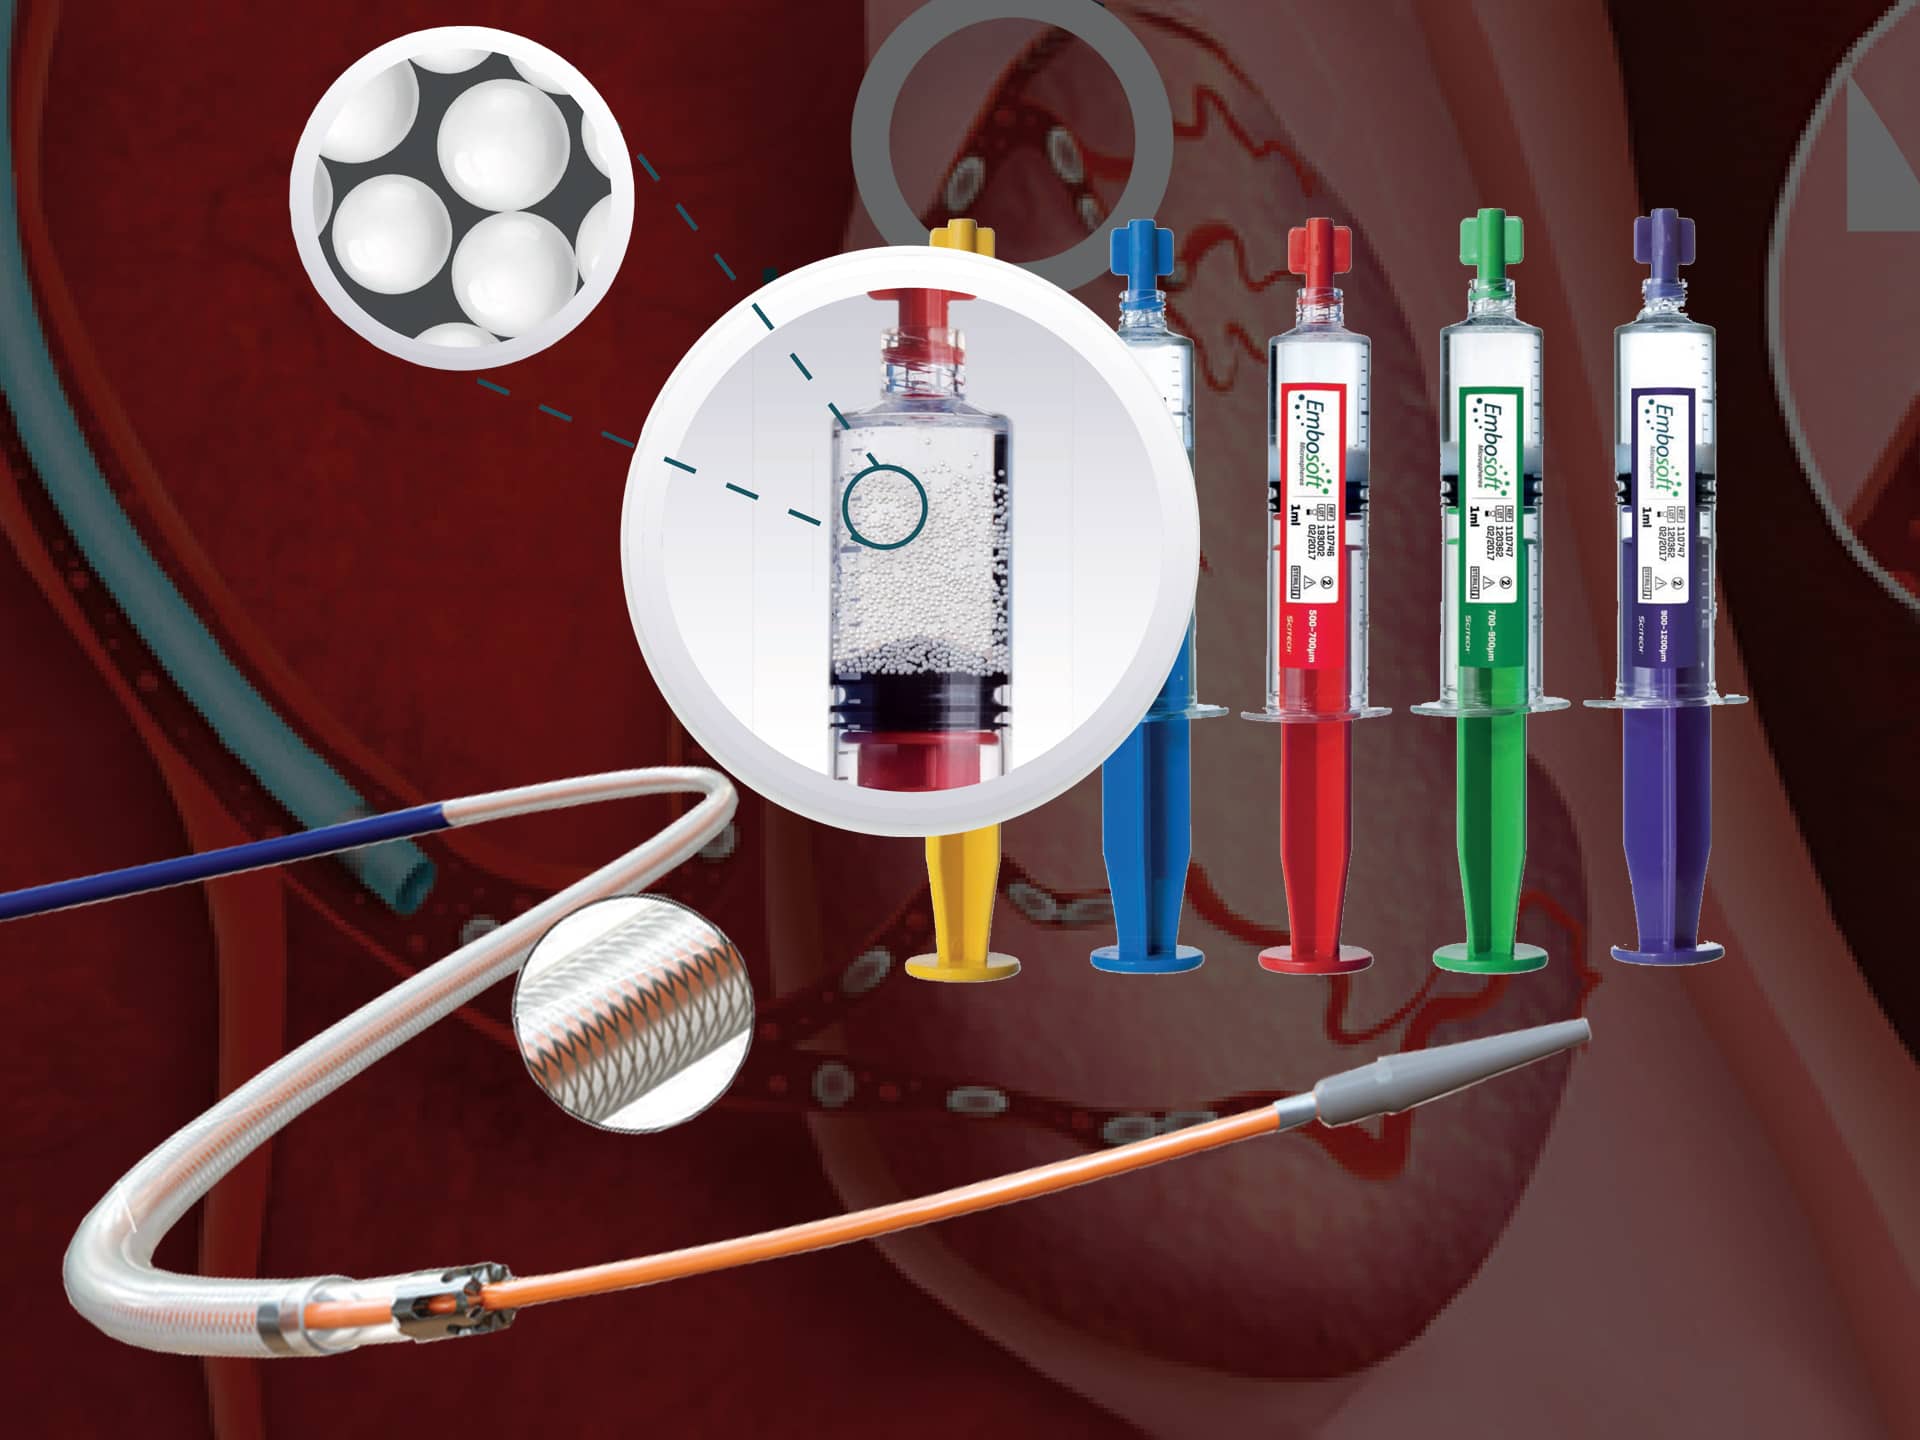

Our Products

Thrombosis is a serious condition where one or more blood clots form in your blood vessels or heart. When this happens, the clot can block blood flow where it formed, or it can break loose and travel elsewhere in your body. If a moving clot gets stuck in a critical area, it can cause life-threatening conditions like stroke and heart attack.